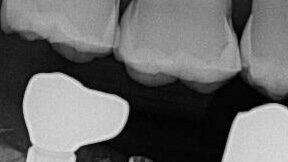

Multiple, Early TiBase Abutment Fractures In Single Tooth Molar Applications – 0045

This case showcases Another Example of Multiple, Early TiBase Abutment Fractures When In Single Tooth Molar Applications.